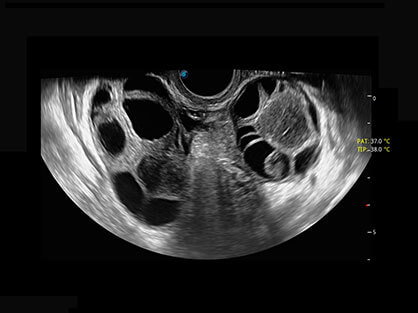

• AVC Follice卵泡自动测量

卵泡结构的自动识别和测量,可显示多组测量数据。